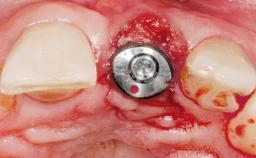

Immediate Placement of an Implant in a Maxillary Left Central Incisor Site

Type of Implants One-Piece

Bone Augmentation Horizontal|Simultaneous

Augmentation Materials Xenogenous|Membrane

Soft Tissue Grafting Simultaneous

Placement Protocol Immediate implant placement

Socket Integrity Damage to one or more bone walls

Bone Volume Damage to one or more socket walls